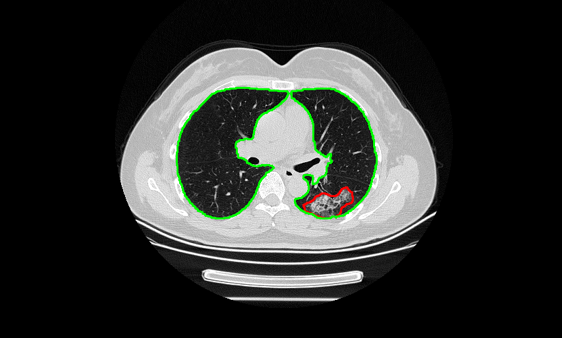

连心医疗基于百度飞桨开发上线"基于CT影像的肺炎筛查与病情预评估AI系统",首先在湖南郴州湘南学院附属医院投入使用。